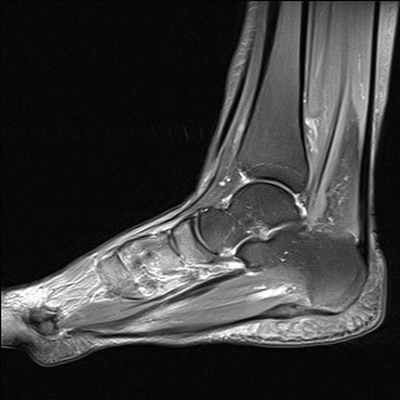

(Левый) При МРТ в коронарной плоскости на Т2ВИ в режиме FS определяются проявления нестабильности подтаранного сустава: ремоделирование костей и субхондральный отек. Также выявляется разрыв ПМС. Вторичная синовиальная кистам послужила причиной развития синдрома канала предплюсны.

(Правый) Пациент, страдающий нестабильностью заднего отдела стопы. При МРТ в коронарной плоскости на Т2 ВИ в режиме FS визуализируются разрывы межкостной связки и ПМС. Волокна глубокого слоя дельтовидной связки не изменены. (Левый) При МРТ в сагиттальной плоскости в режиме STIR определяется утолщенная и подвергшаяся рубцеванию цервикальная связка. Также выявляется подвывих заднего отдела подтаранного сустава. В норме передний край суставной поверхности таранной кости должен соответствовать углу Гиссана, однако в данном случае пяточная кость смещена кпереди.

(Правый) У этого же пациента при МРТ в сагиттальной плоскости в режиме STIR визуализируются разрыв межкостной связки и субхондральный отек таранной кости. При осмотре признаков нестабильности голеностопного сустава выявлено не было. (Левый) При МРТ с контрастным усилением в сагиттальной плоскости на Т1ВИ в режиме FS определяются проявления нестабильности голеностопного сустава: передний подвывих таранной кости, обусловливающий характерную деформацию стопы («стопа клоуна»), синовит и субхондральный отек. Причиной нестабильности послужил ревматоидный артрит.